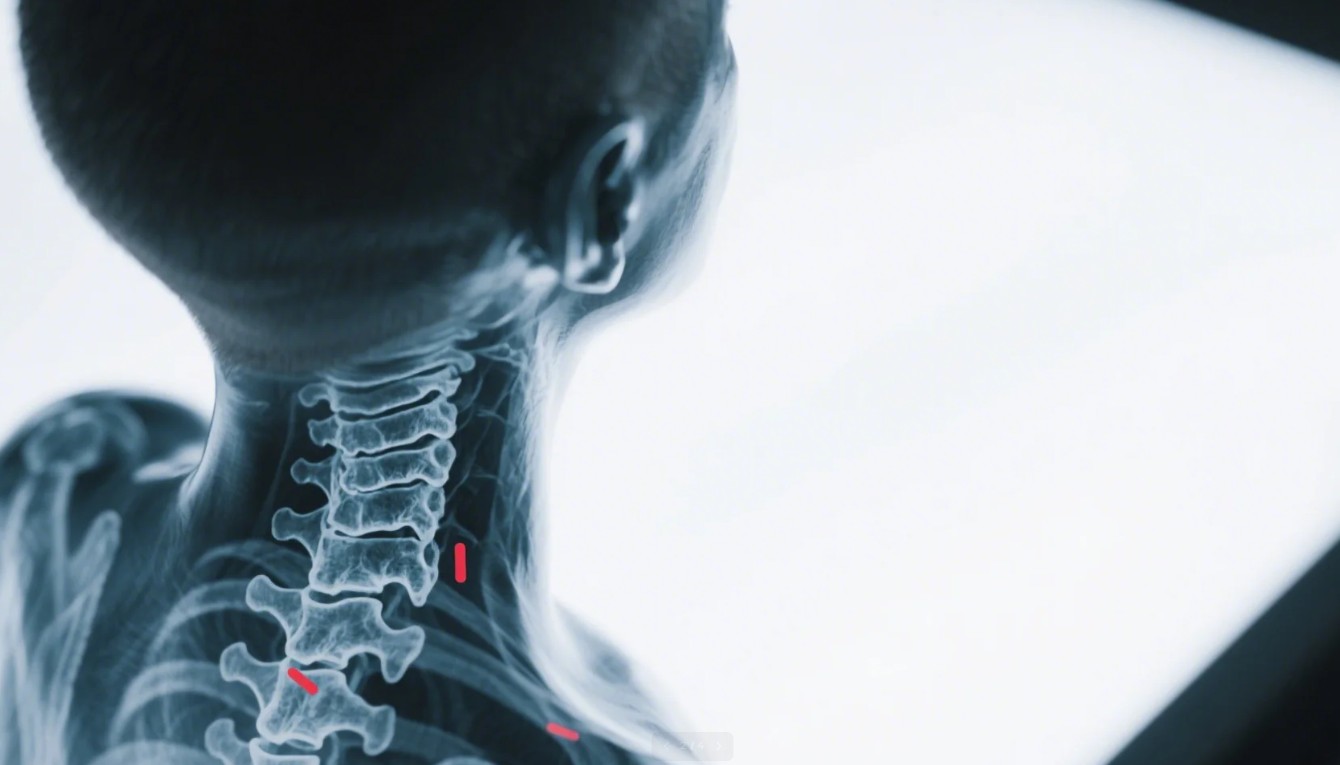

Servikal Lordoz, boyun bölgesinde bulunan omurların doğal eğriliklerini ifade eder. Normalde, boyun bölgesinde hafif bir içe doğru kıvrılma bulunur ve bu yapı omurganın dengesini korumasına yardımcı olur. Ancak, bu doğal eğrilik bozulduğunda çeşitli sorunlar ortaya çıkabilir. Servikal lordoz, bu eğriliğin fazla veya az olmasından kaynaklanan bir durumdur ve çoğunlukla boyun ağrısı ile ilişkilidir. Özellikle modern yaşam tarzı ve duruş bozuklukları, servikal lordoz problemlerinin yaygınlaşmasında önemli bir rol oynamaktadır. Uzun saatler bilgisayar başında çalışmak veya cep telefonu kullanmak, boyun kaslarının gerilmesine ve omurganın dengesizleşmesine yol açabilir. Bu durum, boyun ağrısının yanı sıra baş ağrıları, sırt ağrıları ve diğer fiziksel rahatsızlıklara da neden olabilir. Servikal Lordozun Temel Özellikleri- Boyun omurlarındaki doğal kıvrımın artışı veya azalması.

Servikal Lordoz, boyun omurlarının normalden fazla eğilmesi sonucu oluşan bir durumdur. Bu bozukluk, birçok insanda farklı derecelerde boyun ağrısına neden olabilir. Fizik tedavi ve egzersiz programları, servikal lordozun yönetiminde önemli bir rol oynamaktadır. Bu süreç, kişiye özel bir yaklaşım gerektirmektedir ve doğru tekniklerin uygulanması başarı açısından kritik öneme sahiptir.Hastalığın tedavisinde ilk adım, doğru bir teşhis koymaktır. Fizik tedavi uzmanları, hastanın durumunu değerlendirerek uygun egzersiz ve tedavi planını oluştururlar. Egzersizler, boyun kaslarının güçlendirilmesinin yanı sıra, esnekliğin artırılması ve duruşun düzeltilmesi açısından da büyük fayda sağlar. Ayrıca, hastanın günlük yaşamında doğru postürü sağlaması için farkındalık oluşturulması önemlidir.